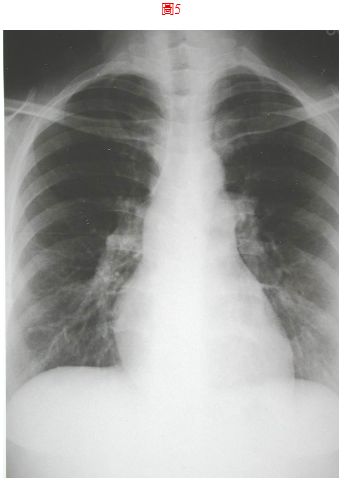

8. 病人26歲男性宜蘭頭城工人,主訴偶有胸悶歷經一個月。他自小開始就不適運動,胸口時有鐘擺劇動,最近常有運動相關的胸悶,伴有心悸眩暈,有時強度運動會有發紺。既往病史未有特別,理學檢查; 身高155cm, 體重45.5 kg, 血壓108/70 mmHg, 心跳80/min, 頸靜脈正常PMI 左5th ICS的LMCL, RV heave, 在左上胸椽有Gr III/VI systolic ejection murmur with fixed splitting S2, 未有心雜音傳移, P2加重。其他理學未有不正常,胸部X光如圖8及心電圖 如圖示,本病人最正確的心臟診斷是

(A) Pulmonary stenosis (B) Idiopathic pulmonary hypertension (C) Atrial septal defect (D) Aortic stenosis (E) Mitral stenosis